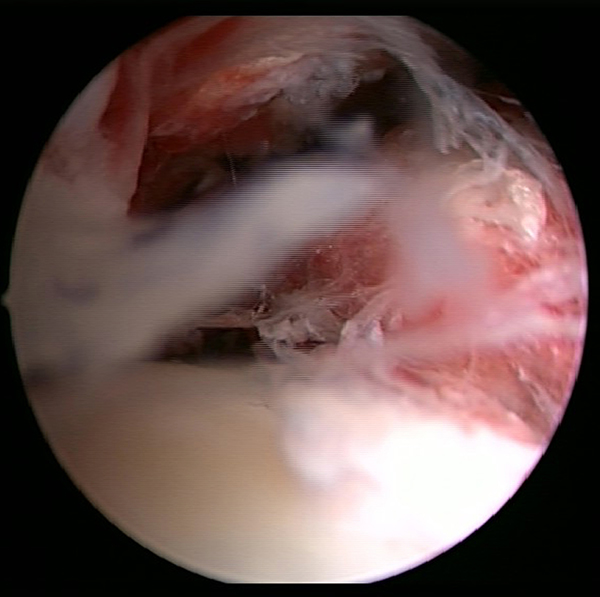

Ein aktuelles systematisches Review zur arthroskopisch-assistierten Frakturversorgung (AORIF) am Sprunggelenk identifizierte bei 495 von 782 Patienten (63,3%) chondrale Verletzungen 54. Weder durch die klinische Untersuchung noch mit konventionellen Röntgenaufnahmen oder mittels CT-Bildgebung lassen sich diese Verletzungen zuverlässig diagnostizieren. Aus diesem Grund rückt die arthroskopisch-assistierte Frakturversorgung am oberen Sprunggelenk zunehmend in den Fokus. Die Arthroskopie ermöglicht im Rahmen der Frakturversorgung sowohl die Kontrolle der Reposition als auch die Beurteilung und Therapie von intraartikulären Pathologien. Während sich die arthroskopisch-unterstützte Versorgung einiger Frakturen bereits etabliert hat (z.B. proximale Tibiafraktur) gehört der Einsatz der Arthroskopie bei der Frakturversorgung des oberen Sprunggelenks in den allermeisten Kliniken noch nicht zum Versorgungsalltag 155 Im Gegenteil, in einer aktuellen amerikanischen Datenbankanalyse des United Healthcare Orthopedic Datasets wurden zwischen 2007 und 2011 insgesamt 32 307 Patienten identifiziert, die mittels ORIF an einer Sprunggelenksfraktur versorgt wurden. In weniger als einem Prozent erfolgte eine arthroskopisch-assistierte Versorgung 55. Dem gegenüber stehen arthroskopische Studien der vergangenen Jahre, die zeigen konnten, wie häufig es zu intraartikulären Verletzungen bei Sprunggelenksfrakturen kommt. Das Risiko für diese intraartikulären Begleitverletzungen nimmt mit der Komplexität der Fraktur zu 5657. Es liegt also nahe, dass bei komplexeren Frakturen die Durchführung einer Arthroskopie im Rahmen der Frakturversorgung einen positiven Effekt auf das Behandlungsergebnis hat. Aus Sicht der Autoren sollte es Ziel für die Zukunft sein, die Frakturtypen zu identifizieren, die von einer arthroskopisch-assistierten Frakturversorgung profitieren. Die diagnostische Arthroskopie mit dem Ziel der gleichzeitigen arthroskopischen Therapie ist in der aktuellen S2-Leitlinie bereits eine Level-1b-Empfehlung. In den Abbildungen 20 – 30 ist schrittweise unser Vorgehen zur arthroskopisch assistierten Versorgung einer Trimalleolarfraktur dargestellt.